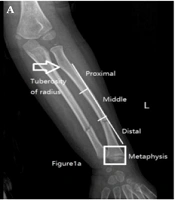

Risk Analysis of Re-displacement After Conservative Treatment of Pediatric Unstable Fractures of Middle and Distal Forearm